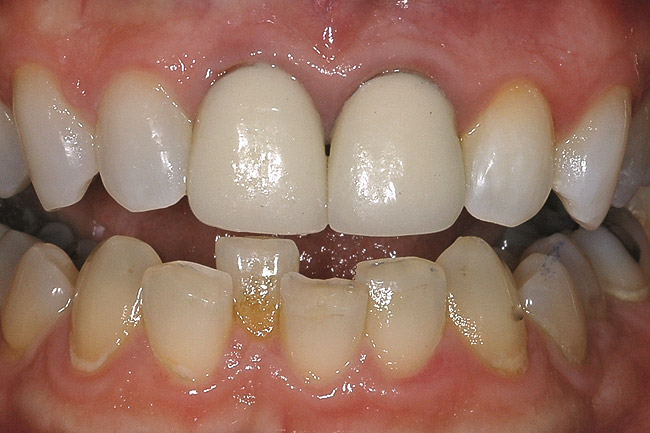

Figure 1  A clinical examination demonstrates a single, very dark lateral incisor and a moderately dark central incisor with a crown on the adjacent central incisor and several dark gingival areas.

Figure 1